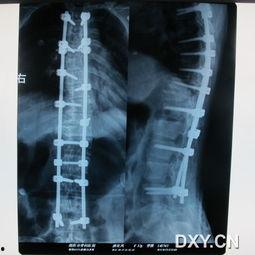

首先,得先给你科普一下什么是脊柱侧弯。简单来说,脊柱侧弯就是人的脊柱在X光片上呈现出S形或C形的弯曲。这种弯曲可以是先天性的,也可以是后天形成的。而今天我们要说的,就是成人脊柱侧弯50度的情况。

视频中,医生首先对主人公进行了详细的问诊和检查。通过X光片,医生发现她的脊柱确实存在侧弯现象。接着,医生还对她进行了体格检查,包括观察她的姿势、活动范围等。

此外,医生还建议她进行手术治疗。由于脊柱侧弯程度较高,手术治疗是必要的。手术过程中,医生会对她的脊柱进行矫正,并固定在正确的位置。